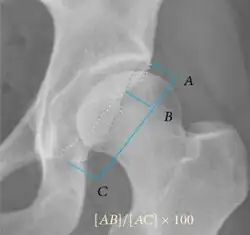

| Crossing ratio |

|

Percentage of acetabular walls crossing. Normal acetabulum is oriented in anteversion. Its value ranges from 15 to 20° in the equatorial plane of the acetabulum and decreases gradually towards the acetabular roof, where normal values range from 0 to 5°. Retroversion of the upper part of the acetabulum has been related with pincer type impingement. In radiography the presence of a "crossover sign" is produced when the posterior wall of the acetabulum crosses the anterior wall before reaching the acetabular roof. It is a sign of acetabular retroversion and it has been linked with overcoverage and pincer impingement. Nevertheless, this sign has been described in 6% of the normal population. Therefore, more important than its presence is the percentage of crossing. | <20%

|